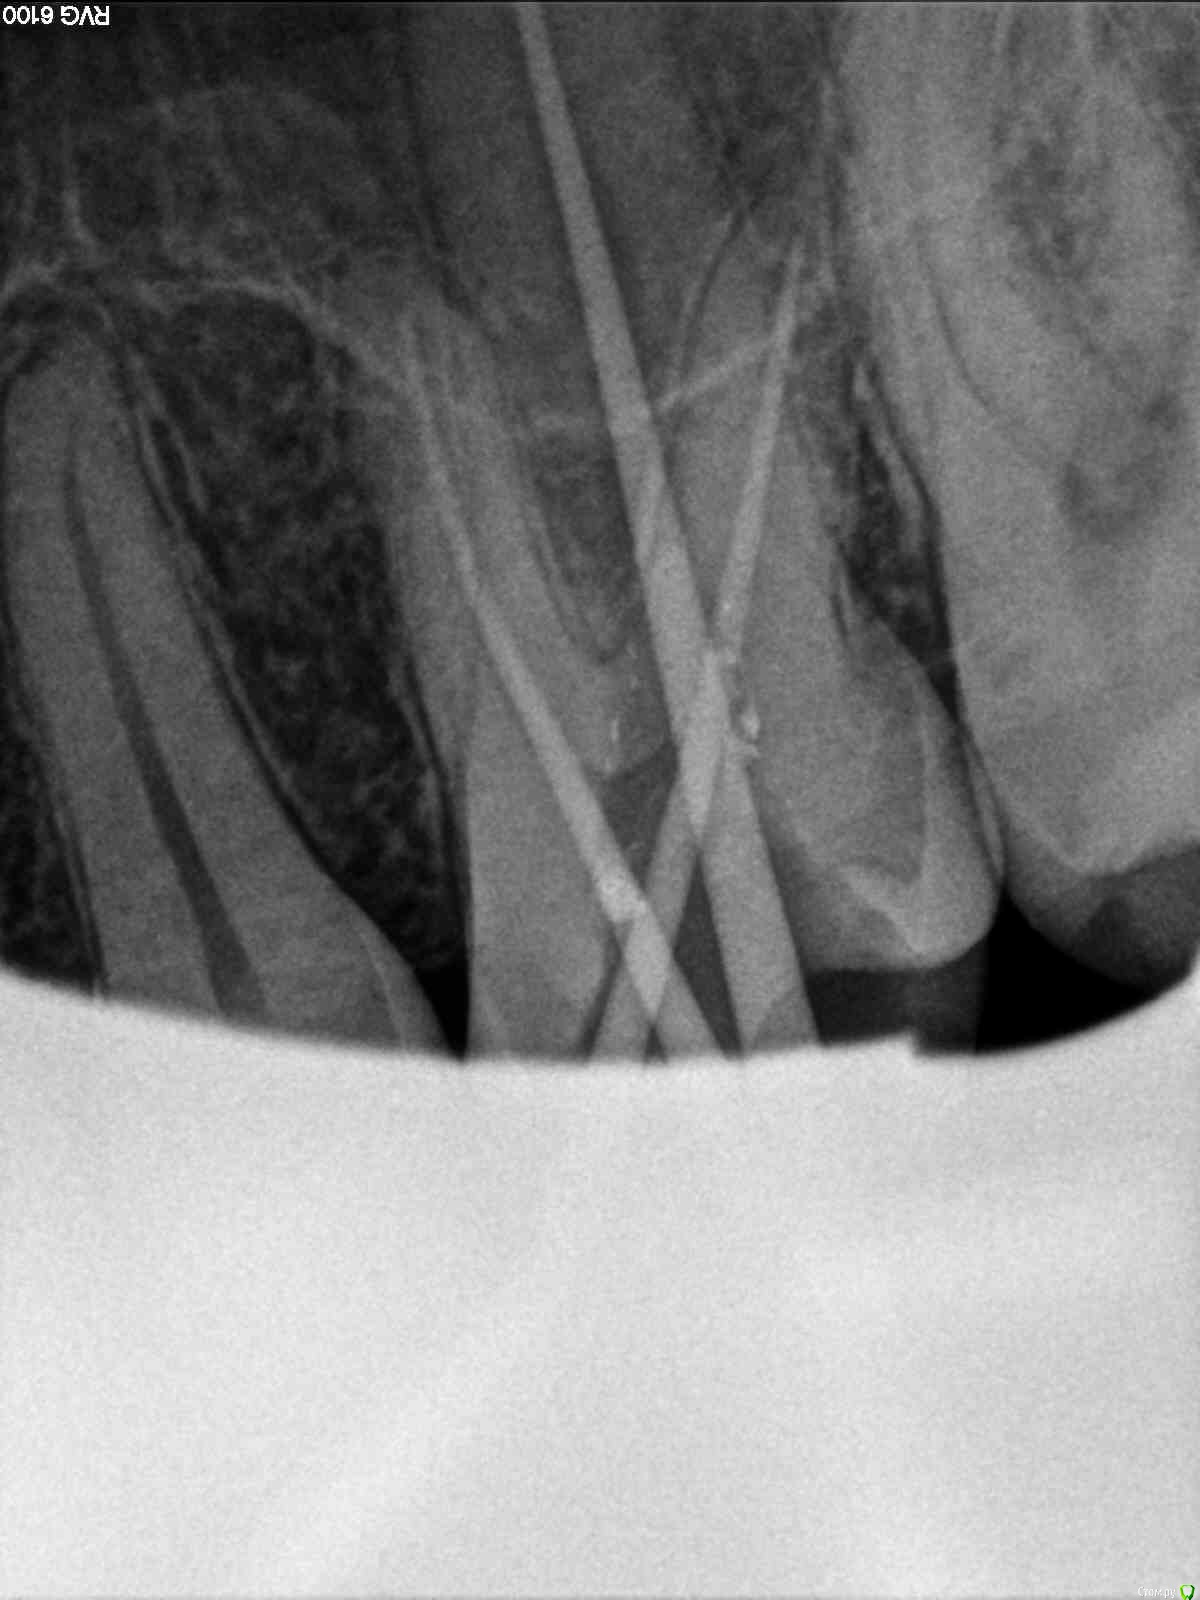

SolnceSamara Опубликовано 24 октября, 2015 Поделиться Опубликовано 24 октября, 2015 почернела старая пломба в давно пролеченной шестерке (сверху). Врач заменила пломбу но зуб болел при надавливании, заменили пломбу повторно-все равно осталась боль, сменила врача-снова сменили пломбу-снова болит, решили депульпировать-снова вынули пломбу, поставили временную-неделю проходила с временной-через неделю окончательно депульпировали, поставили постоянную. Сначало поболело 3 дня, и вроде прошло, хотя остался дискомфорт при надавливании. Прошло 3 недели, боль усилилась, теперь болит не только при надавливании иногда просто звеняще-ноющее ощущение нарастает. Пью нимесил. Посоветуйте что делать-что не так? Снимки прилагаю-делали на протяжении всйх операций (до и после).Разьяснение по снимкам :R1-29/08/15R2,R3-25/09/15R4-R7-28/09/15 Ссылка на комментарий

red_butler Опубликовано 24 октября, 2015 Поделиться Опубликовано 24 октября, 2015 Коллеги поправят, но выглядит как пломбирование одиночным штифтом. Возможно пропущен четвертый канал. Нужна ревизия корневых каналов. 2 Ссылка на комментарий

DmitrySH Опубликовано 24 октября, 2015 Поделиться Опубликовано 24 октября, 2015 Коллеги поправят, но выглядит как пломбирование одиночным штифтом. Возможно пропущен четвертый канал. Нужна ревизия корневых каналов. Все верно. Ссылка на комментарий